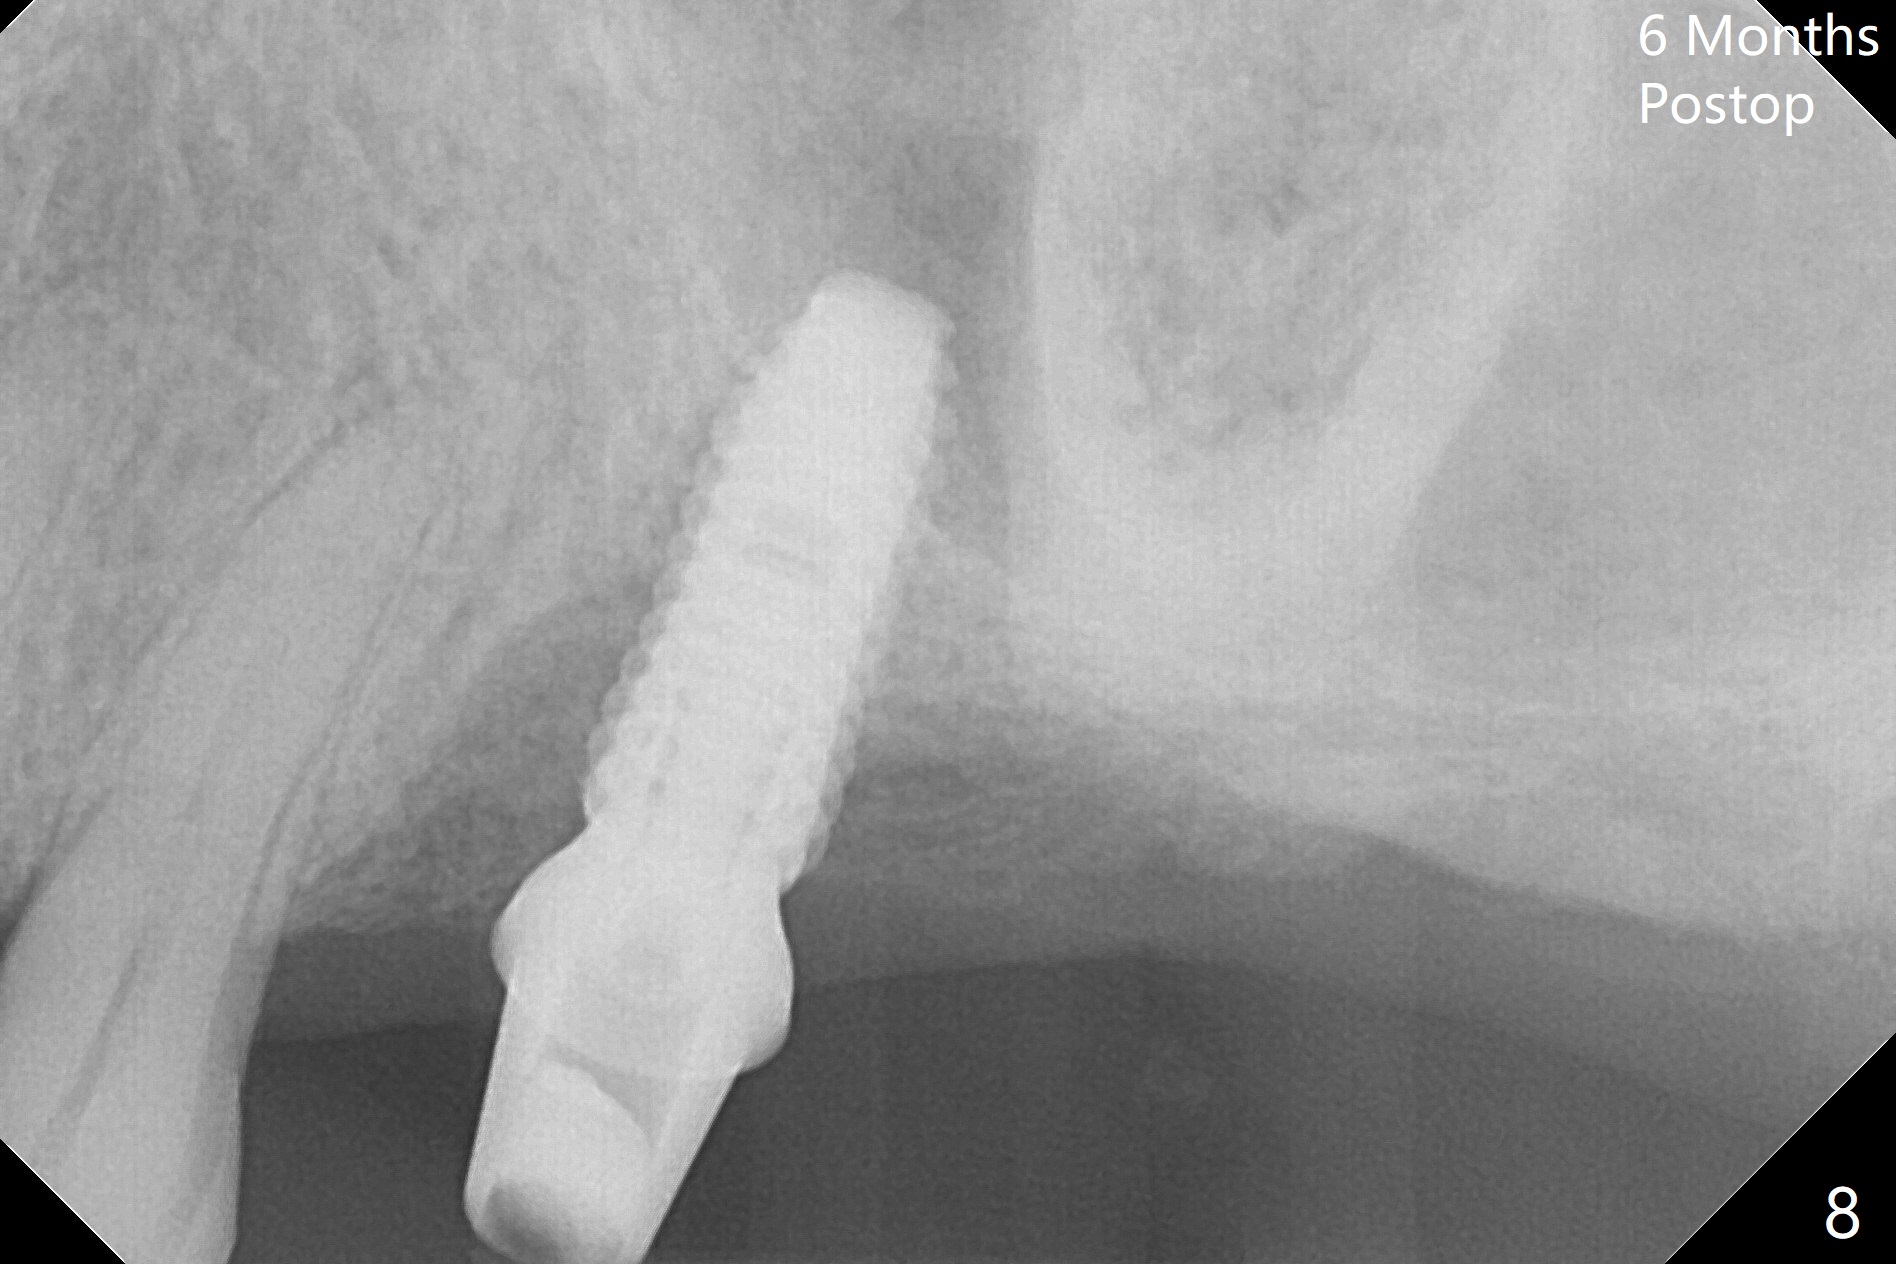

Buccal gingival recession at #14 (Fig.1) is less severe than the palatal one (Fig.2). Without raising the buccal gingiva (Fig.3 B), osteotomy in the septum is established apparently in the middle socket (Fig.3 *, 4). As the osteotomy increases with 3.8 mm drill, the palatal wall of the osteotomy starts to be perforating. When a 4.5x11.5 mm implant is placed, palatal threads are exposed, to which autogenous bone and Vera Graft are placed (Fig.5 *). After placement of a 5.5x5(3) mm abutment, an immediate provisional (Fig.6 P) is fabricated to cover the sockets. If the septal dimension were studied carefully by raising the buccal gingiva slightly, the osteotomy could be initially more buccal so that the palatal thread exposure could be less. When the provisional is removed 1.5 months postop, the implant is exposed palatally. The margin of the provisional is modified so that the implant can be cleaned by the patient using Water Pik. In fact, the healthy gingiva seems to be attached to the implant threads 2 weeks later (Fig.7). The distal implant threads remains exposed 6 months postop; it appears that the distal socket wall has resorbed (Fig.8). The sockets heal 1 year 7 months post cementation (Fig.9).